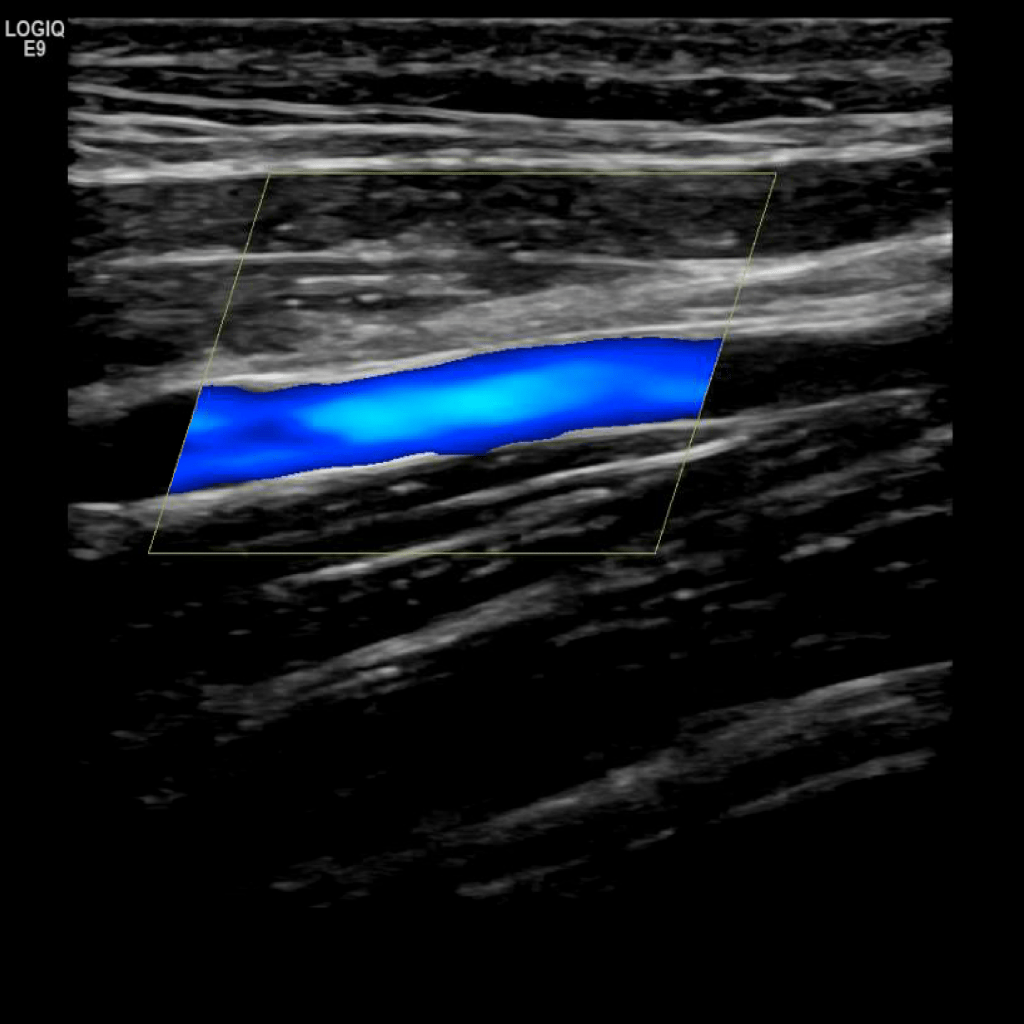

A typical scanning protocol includes transverse and sagittal images with and without color doppler and spectral wave analysis of the IJV, subclavian, axillary, brachial, basilic, cephalic, radial and ulnar veins. In my institution we include innominate and superior vena cava (SVC) in the vessels we interrogate.

Scan the subclavian vein in grey scale, color doppler and spectral doppler

Scan the axillary vein in grey scale, compression, color doppler and spectral doppler

Scan the basilic vein in grey scale, compression, color doppler and spectral doppler